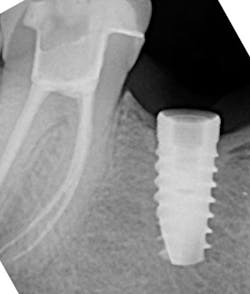

There are many different types of screw/implant retrieval and rescue kits made by different companies. Nobel Biocare, Neobiotech, Osstem (OssVK), BTI Biotechnology Institute, and Salvin Dental Specialties all make these types of kits. The author has found great success with screw retrieval using the Implant Rescue Kit from Salvin Dental (figure 3). This kit is especially useful when the broken screw is fractured in the apical 50% of the implant chamber (figure 4). Following are the steps involved in using this implant screw retrieval kit (figure 5).

- Insert the appropriate drill guide onto the implant platform. Use a contra-angle handpiece with the pilot drill at 1,000–1,250 RPM in reverse with a pumping motion and copious irrigation to create a 1–2 mm deep dimple into the fractured screwhead. This creates a purchase point for the next drill tap.

- Suction the metal shavings and irrigate the area.

- While still in reverse, use the tap drill at 70–80 rpm, which will reverse out the broken screw from the screw chamber.